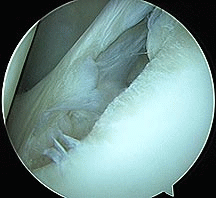

Bankart Lesion after repair